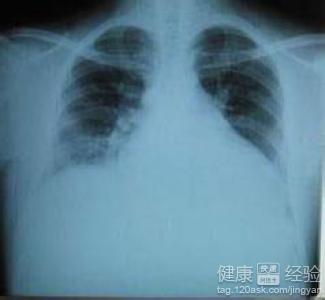

左心明顯增大心肌病哪裡能治

1現在很多人在患上該疾病的時候,會喜歡用中醫治療,因為中藥治療不僅可以治療該疾病,更重要的是還可以達到調養身體的效果。這種疾病分為兩種,有原發性心肌病和繼發性心肌病,並且病理也分為好幾種。